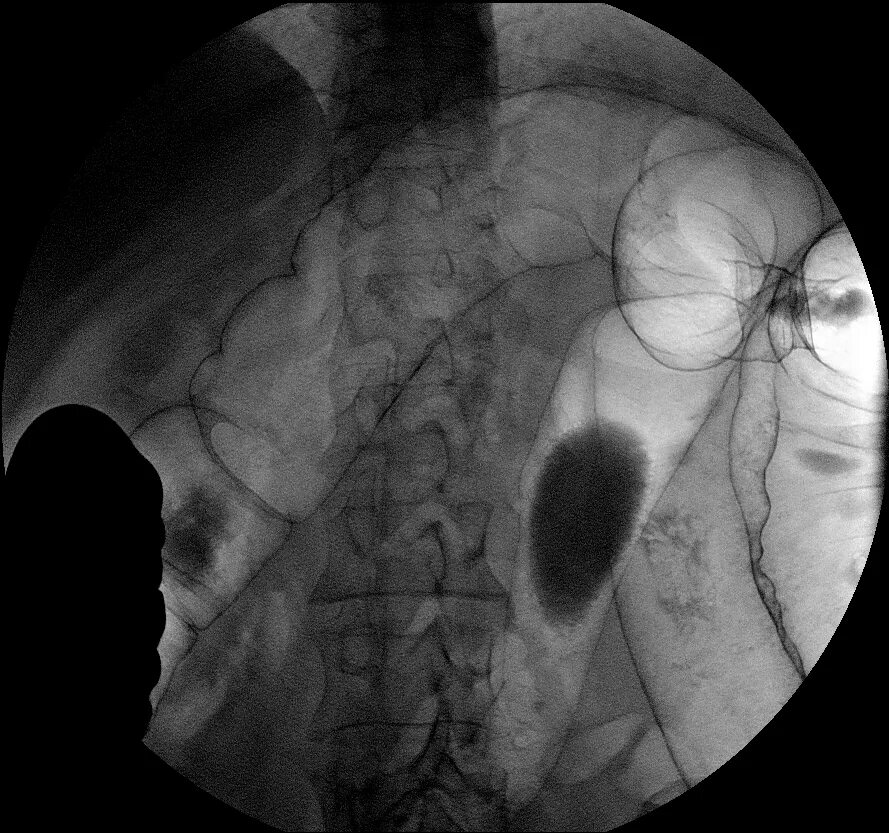

Ирригоскопия с двойным контрастированием